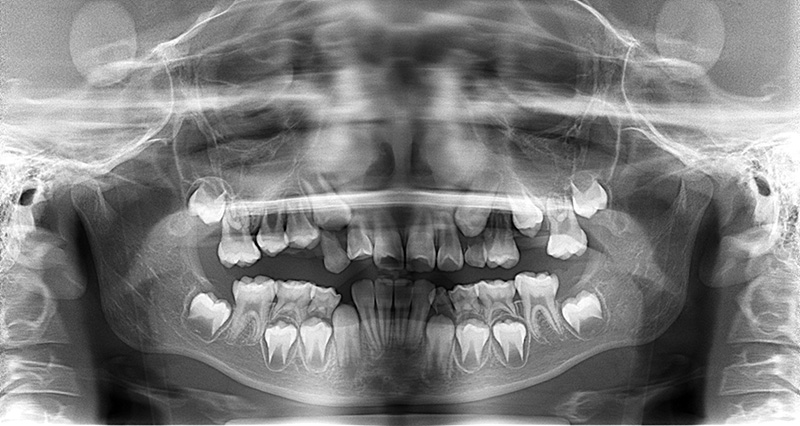

| パノラマ所見 | 上顎両側6、特に左側6は近心傾斜が認められ、両側5の萌出スペース不足が認められた。 |